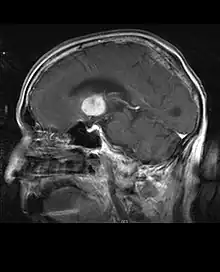

La tomodensitométrie (TDM) et L'imagerie par résonance magnétique (IRM) peuvent détecter efficacement une néoplasie dans le cerveau. L'IRM est plus sensible que la TDM pour identifier les lésions, mais présente des contre- indications pour les patients porteurs de stimulateurs cardiaques, de prothèses incompatibles, de clips métalliques et contre-indications. La TDM reste la méthode de choix pour détecter les calcifications au sein des lésions ou les érosions osseuses de la calotte ou de base du crâne. L'utilisation d' agents de contraste, iodés dans le cas du scanner et paramagnétiques (gadolinium) dans le cas de l'IRM, permet l'acquisition d'informations sur la vascularisation et l'intégrité de la barrière hémato-encéphalique, une meilleure définition de la tumeur tumorale par rapport à l' œdème environnant et à la génération d' hypothèses sur le degré de malignité. L'examen radiologique permet également d'évaluer les effets mécaniques et les modifications importantes des structures cérébrales résultant de la tumeur, telles que l' hydrocéphalie et les hernies, dont les effets peuvent être fatals. Enfin, en préparation à la chirurgie, ce diagnostic peut être utilisé pour déterminer la localisation de la lésion ou l'infiltration de la tumeur dans des zones vitales du cerveau. À cette fin, l'IRM est plus efficace que la tomodensitométrie car elle peut fournir des images en trois dimensions.

Les outils d'imagerie radiologique diagnostique mettent en évidence la modification du tissu néoplasique par rapport au parenchyme cérébral normal (par le biais de modifications de la densité tissulaire imagée électroniquement en TDM et de l'intensité du signal en IRM). Comme la plupart des tissus pathologiques, les tumeurs sont également reconnaissables par une accumulation accrue d'eau intracellulaire. Dans la tomodensitométrie, ils apparaissent hypodenses, c'est-à-dire de moindre densité que le parenchyme cérébral, dans la tomographie par résonance magnétique nucléaire avec relaxation spin-réseau hypointense et en relaxation spin-spin ainsi que l' hypersignal en pondération protonique (PD).

La zone saine du cerveau ne doit présenter aucune luminescence particulière sur une image radiologique. Par conséquent, il va sans dire que l'attention est portée sur des plages de signaux de contraste plus larges.

Dans le tissu tumoral, en général, la plus grande proportion d'amélioration du contraste est due à la barrière hémato-tumorale particulière qui permet le passage de l'iode (CT) et du gadolinium (IRM) dans l'espace interstitiel extravasculaire intratumoral. Cela augmente le signal (densité ou intensité) de la tumeur. Cependant, des précautions doivent être prises pour s'assurer que l'amélioration du contraste ne différencie pas définitivement la néoplasie de l'œdème péri-lésionnel. En fait, la découverte anatomo-pathologique dans le tissu tumoral infiltrant malin du gliome, comme dans le glioblastome et l'astrocytome anaplasique, montre également au-delà de l'œdème vasogénique causé par la destruction de la barrière hémato-encéphalique par la tumeur. Cette dernière condition clinique est difficilement détectable par imagerie diagnostique.

La tomodensitométrie du cerveau montre généralement une masse tissulaire qui peut être améliorée par l'un ou l'autre contraste. Au scanner, les gliomes de bas grade apparaissent généralement isodenses au parenchyme normal et peuvent donc ne pas présenter de rehaussement de contraste. De même, les lésions de la fosse crânienne postérieure sont difficiles à identifier au scanner. Par conséquent, les seuls résultats d'une telle tomographie ne sont pas toujours suffisants à des fins diagnostiques. Dans les cas douteux, l'utilisation de l'imagerie par résonance magnétique plus sensible est indispensable.

Sur-L'IRM montre une tumeur intracrânienne comme une lésion massive qui peut devenir plus luminescente après utilisation du produit de contraste. Cependant, il y a toujours une anomalie de signal dans -L'imagerie par résonance magnétique, qui indique la présence d'une néoplasie ou d'un œdème vasogénique. Habituellement, une luminescence accrue (amélioration du contraste) indique une tumeur d'un grade supérieur de malignité. Un anneau de contraste est caractéristique du glioblastome, avec la partie luminescente correspondant à la partie vitale de la tumeur maligne, et la plus foncée - zone hypointense correspondant à une nécrose tissulaire.